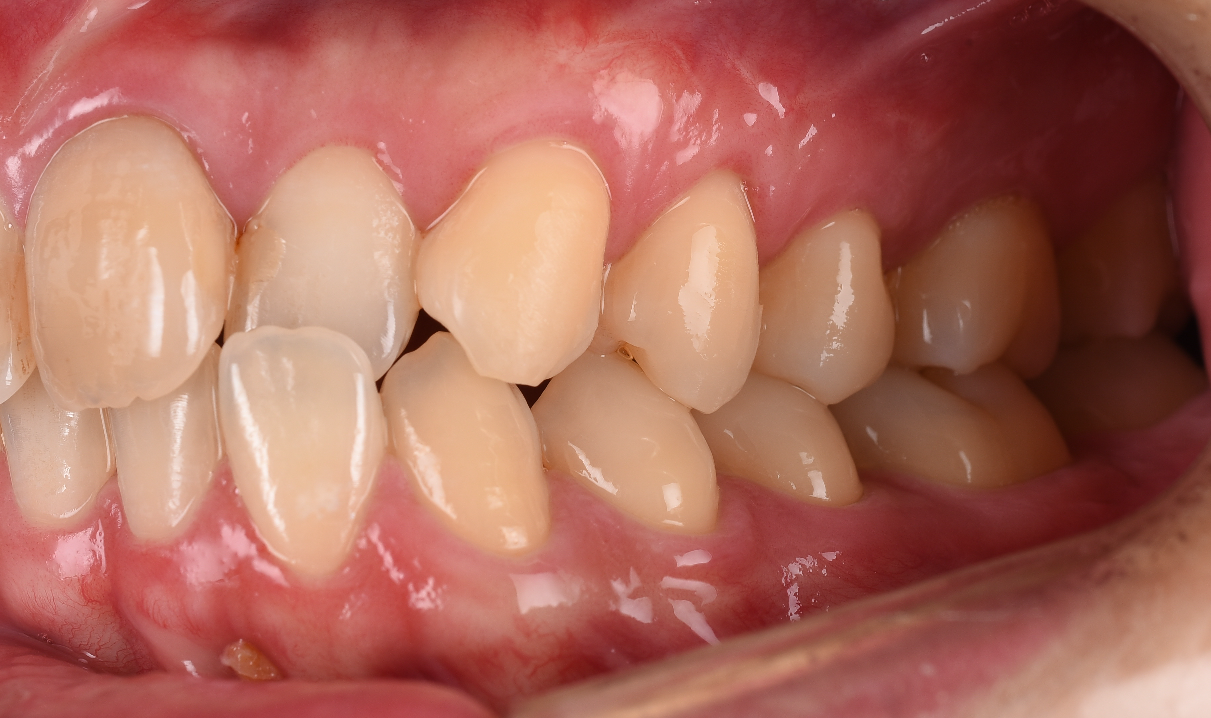

手術2週間後の写真です。

こんなに綺麗になります。

エンベロップで手術していますのでほとんど切っていません。

切っていませんよね。だから痛くありませんし、腫れません。

マイクロスコープを使用する事で体には侵襲をせず、このような状態にもっていく事が可能です。